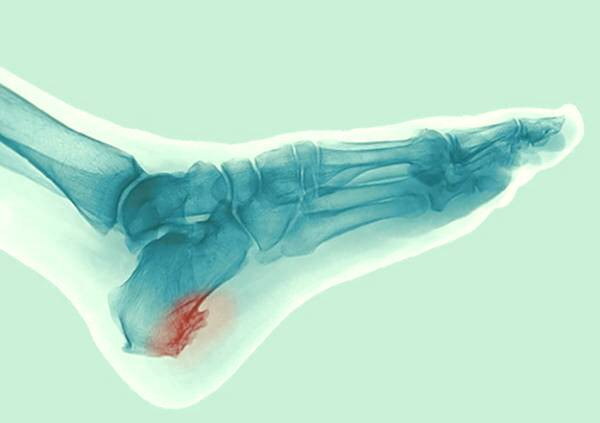

خار پاشنه معمولا با چشم غیرمسلح دیده نمی شود. متخصص و جراح ارتوپدیبرای تشخیص دقیق و صحیح این بیماری، عکس برداری و تصویربرداری ایکس- ری را تجویز می کند. پزشک پا راقبل از انجام آزمایشات و تصویربردار معاینه خواهد کرد تا هرگونه علائم قرمزی یا التهاب را در آن مشاهده کند.